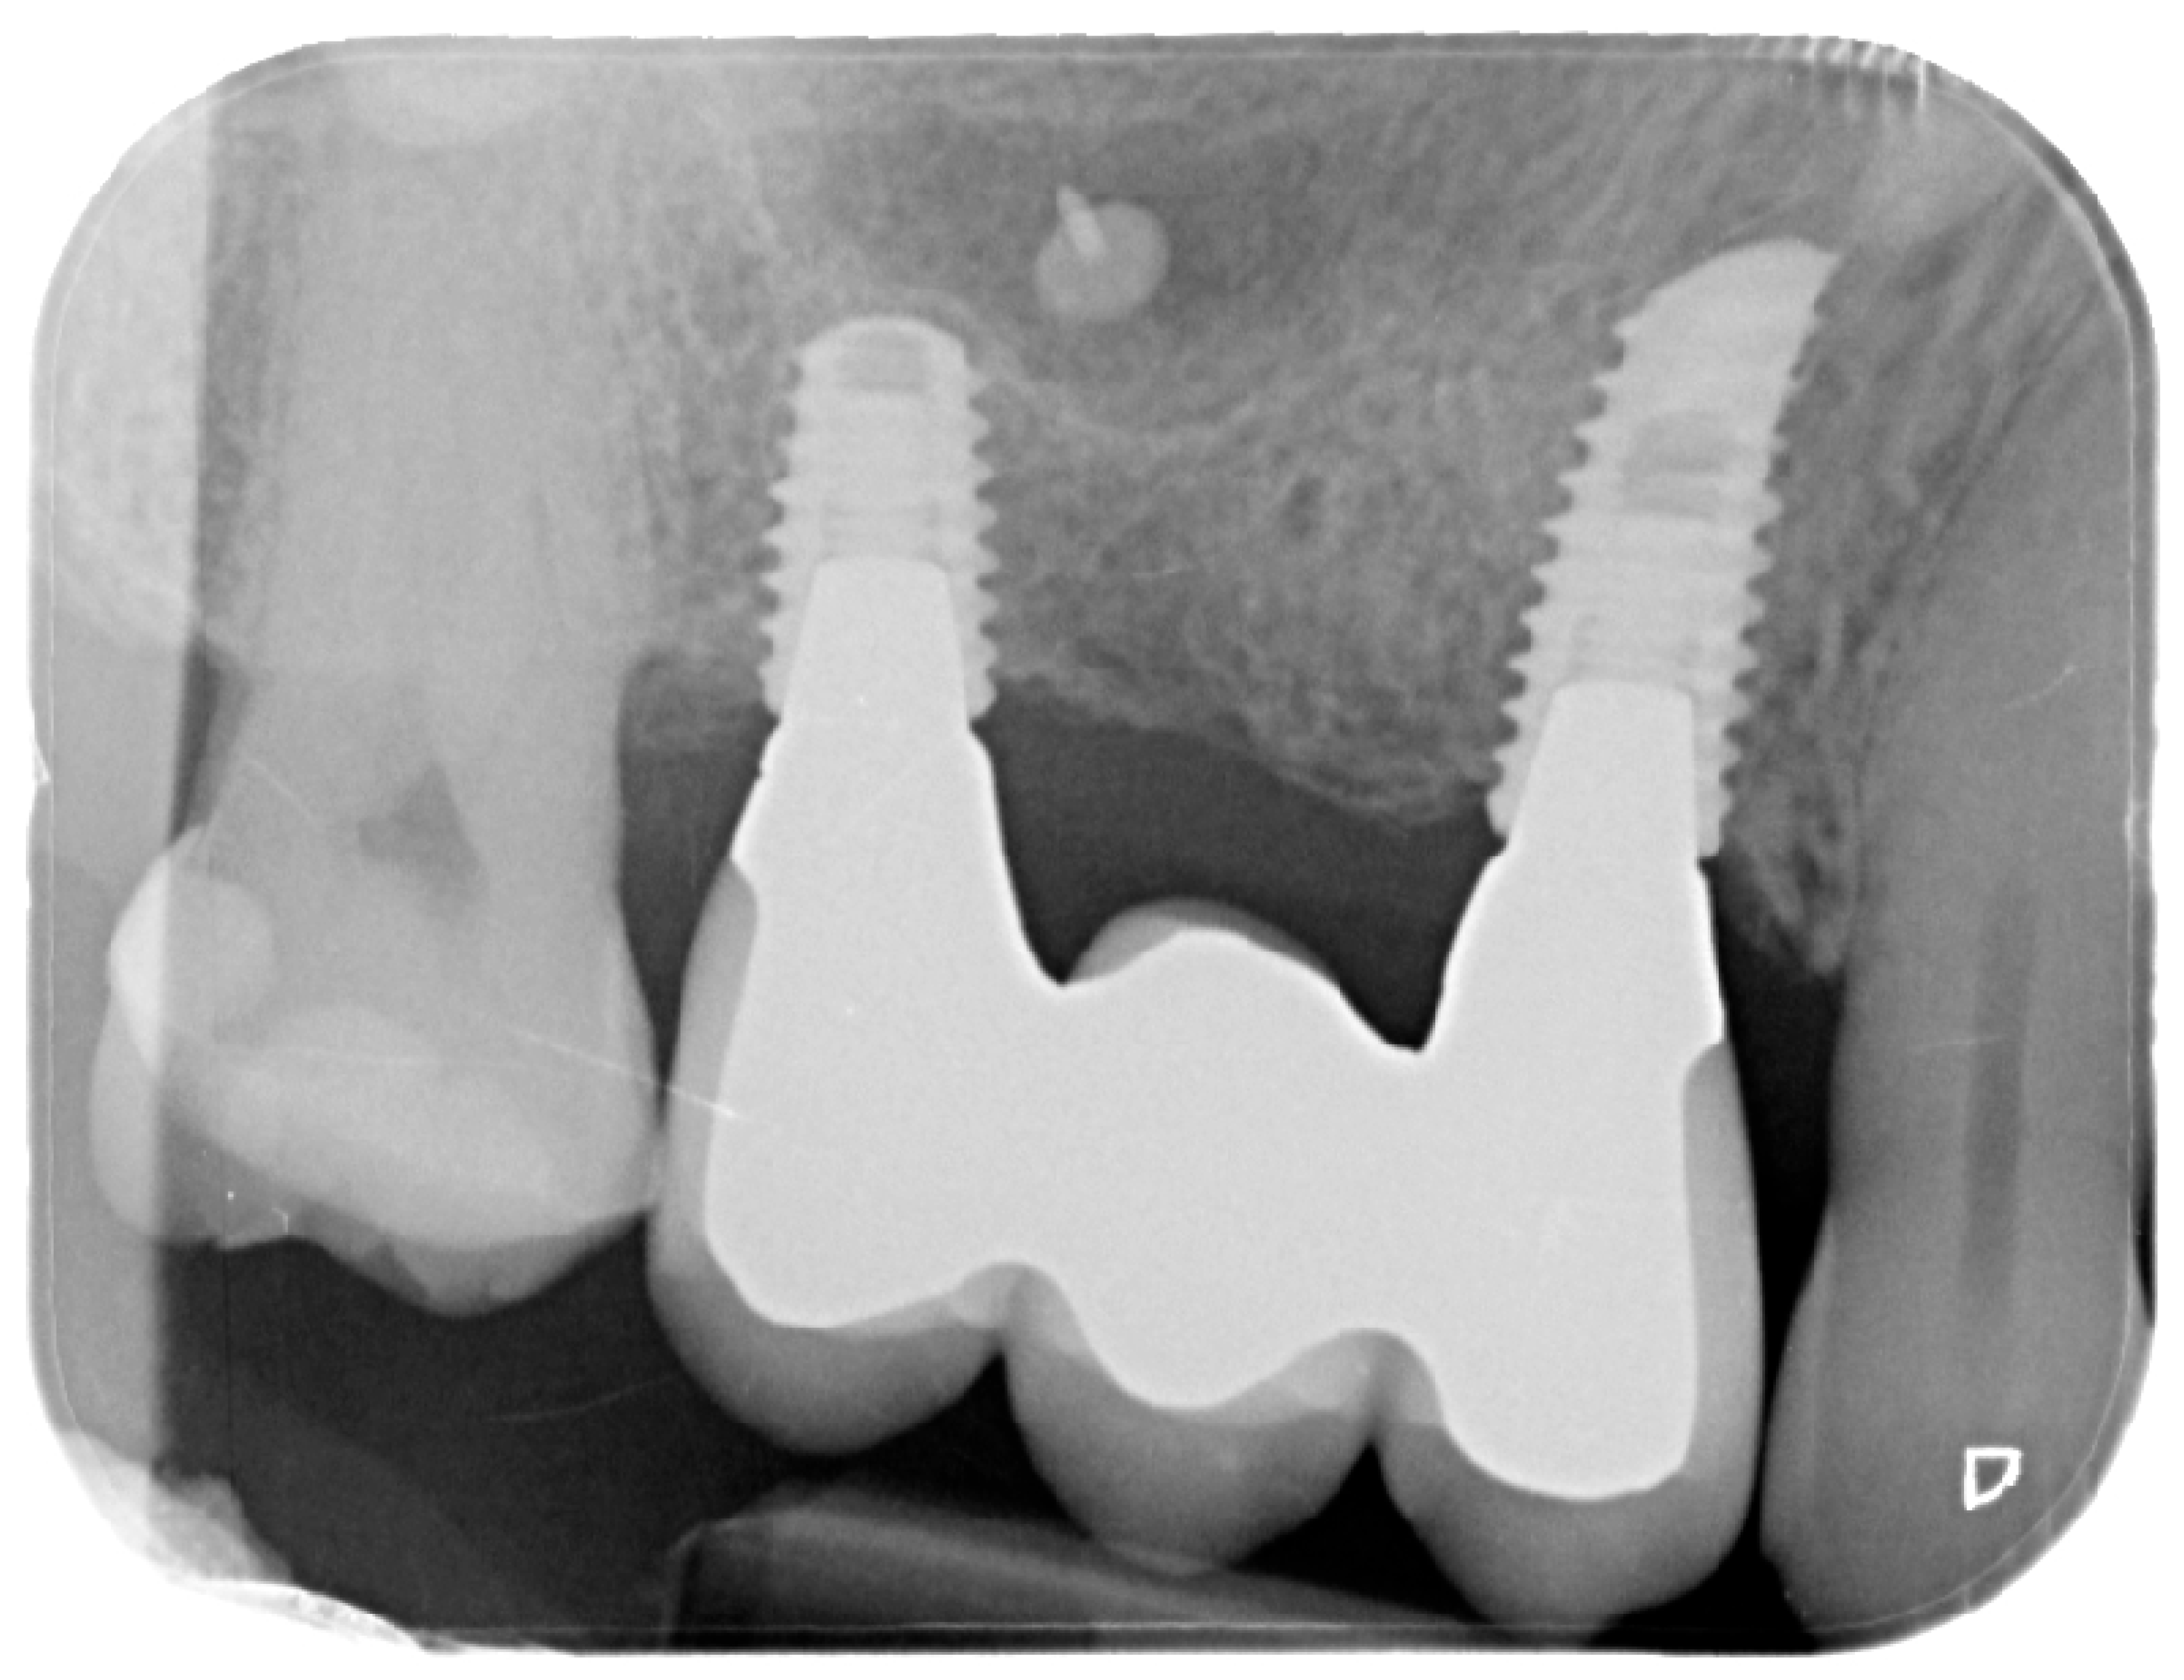

Figure 12.

Intraoral X-ray at delivery of the final prosthesis.

Figure 13.

Intraoral X-ray at one year follow-up.

For the evaluation of the mesial and distal MBL, intraoral digital radiographs were taken using the long-cone paralleling technique with the central beam directed to the alveolar crest. Periapical radiographs were taken at the delivery of the prosthesis and after 1 year of prosthetic loading (T2). The mesial and distal MBL, i.e., the distance between the top of the implant shoulder and the first visible bone-to-implant contact, were measured at the mesial and distal aspect with a 10–15× magnification using an image analysis programme (ImageJ v 1.49, NIH, Bethesda, MA, USA). The length of the implant was used as known measure for the calibration and determination of the exact magnification and distortion of the images. All measurements were performed by two examiners to the nearest 0.1 mm. In case of disagreement, the evaluation was re-done and results discussed until an agreement was found.